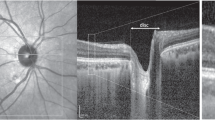

Optical property maps resembling quantitative histology

Figure 1 shows the histology and optical property maps for somatosensory cortex. Gallyas Silver stain (Fig. 1a) exhibits contrast among the supragranular layers which consist of pyramidal neurons, numerous stellate neurons and sparse axons (indicated by blue region), infragranular layers with large pyramidal neurons and axon bundles that connect to the subcortical structures (green region), and the white matter (red region), which mainly consists of highly myelinated axon bundles and glial cells. The Gallyas Optical Density (OD) map (Fig. 1b) demonstrates that the supragranular layers have the lowest OD value, followed by the infragranular layers which have intermediate amount of myelinated axon bundles. The white matter exhibits the highest OD value due to the highly myelinated and densely packed axonal bundles. In addition, smaller features can be seen in the Gallyas OD map as well, such as the thin band of denser myelin content at the upper right region of layer IV (red arrow), possibly due to the high-density fibers in the outer band of Baillarger29. The Nissl stain and Cellular Occupation per Area (COPA) map (Fig. 1c,d) show contrast for cell bodies. The external granular layer (layer II) and the external pyramidal layer (layer III) exhibit the highest COPA value (red region), especially in the lower left part of the sample (black arrow), probably due to the higher neuron density. The internal granular layer (layer IV), internal pyramidal layer (layer V), and the fusiform layer (layer VI) present alternating contrasts (small green arrows). The white matter generally exhibits a low value of COPA, which is mainly attributed to the glia cells.

Histology and OCT optical property maps of the human somatosensory cortex. (a) Gallyas Silver stain shows contrast for myelin content. Red region: white matter. Green region: infragranular layers consist of layer IV, V and VI. Blue region: supragranular layers consist of layer I, II and III. Red arrow indicates a thin band of higher myelin content inside layer IV. (b) Optical density (OD) of Gallyas silver stain. The red arrow highlights the myelinated band inside the layer IV. (c,d) Nissl statin and COPA show contrast for cell bodies. The red region indicates the layer II and III with highest COPA value. The big black arrow highlights the high neuron density region. The small green arrows highlight the IV, V, VI layers within the infragranular layer with alternating contrasts. (e–g) Optical properties derived from the OCT images. (e) \({\mu }_{s}\) map. Small green arrows highlight the alternating contrasts in the infragranular layers similar to that in the COPA map, and the big red arrow indicates the myelinated band seen in Gallyas OD map. (f) \({\mu {^{\prime}}}_{b}\) map. Green arrow highlights the fibers with high intensity, possibly oriented within the imaging plane. (g) Ratio map of \({\mu {^{\prime}}}_{b}/{ \mu }_{s}\) . Green arrow highlights the fibers with high intensity, similar to that in the \({\mu {^{\prime}}}_{b}\) map. The Blue arrow highlights the region with high signals in the supragranular layers. (h) OCT average intensity projection (AIP) image.

The \({\mu }_{s}\) map (Fig. 1e) strongly resembles the Gallyas OD map. The white matter shows highest \({\mu }_{s}\) because of the highly scattering myelin sheath. As the sparse axon branches into the cortex, \({\mu }_{s}\) decreases accordingly. The supragranular layer shows the lowest \({\mu }_{s}\), due to the lack of myelin content. In addition, the thin band feature at the upper right region (red arrow) found in Gallyas OD map can also be seen in the \({\mu }_{s}\) map. Apart from that, the infragranular layers (IV, V, VI) show additional laminar structures (small green arrows) similar to the COPA map but not in Gallyas OD map. Overall, the \({\mu }_{s}\) map seems to be strongly correlated with myelin content and slightly modulated by the neuron scattering. The \({\mu {^{\prime}}}_{b}\) map (Fig. 1f) offers another feature dimension to aid in discriminating tissue types. It is noticeable that \({\mu {^{\prime}}}_{b}\) varies within the white matter, possibly highlighting fibers oriented within the image plane (green arrow). This is possibly because the fibers oriented within the imaging plane direct more back-scattered photons to the detectors than the fibers oriented through the imaging plane. Consequently, the \({\mu {^{\prime}}}_{b}\) map offers potential information about fiber orientation. The ratio of \({\mu {^{\prime}}}_{b}/{ \mu }_{s}\) map (Fig. 1g) provides another useful feature to distinguish structures in the brain. Similar to the \({\mu {^{\prime}}}_{b}\) map, the ratio of \({\mu {^{\prime}}}_{b}/{ \mu }_{s}\) map also highlights the region with fibers oriented within the imaging plane (green arrow). In addition, the ratio of \({\mu {^{\prime}}}_{b}/{ \mu }_{s}\) map also highlights region of higher value in the superficial layers indicated by the blue arrow, the cause of such contrast requires further investigation. The AIP image (Fig. 1h) is a nonlinear function of the \({\mu }_{s}\) and \({\mu }_{b}\) maps, which provides an overall view of the tissue structure for reference.